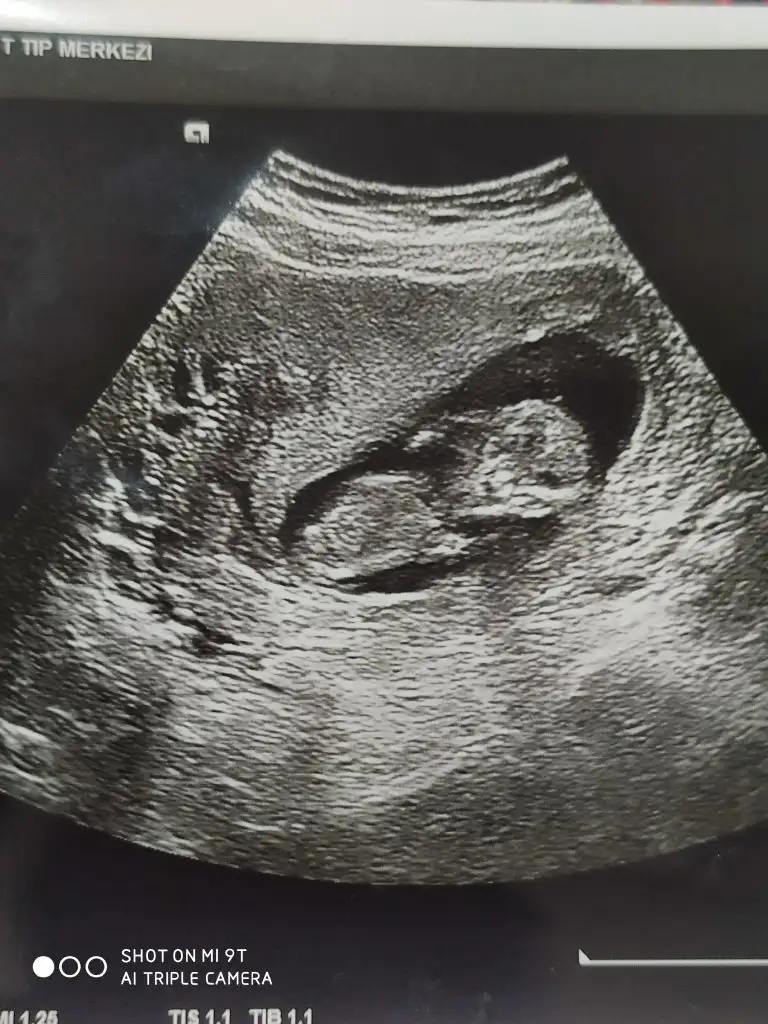

8 haftalık budaBaşka USG paylaşın![]()

Karından ise erkek vajinalsa kiz tabiki en iyi 11 12 13 haftalar8 haftalık buda

Karından bakıldı sonucu alınca yazarım size çok teşekkür ederimKarından ise erkek vajinalsa kiz tabiki en iyi 11 12 13 haftalar